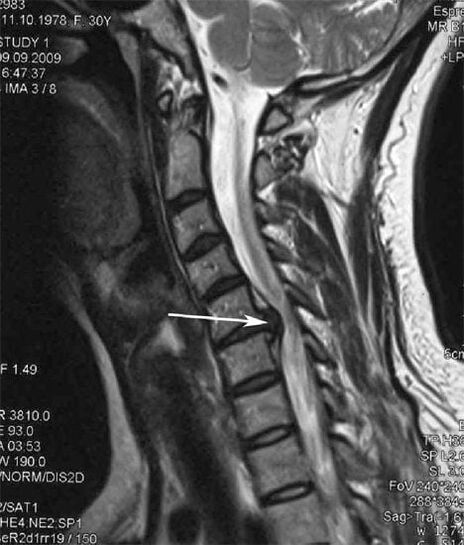

Dans les premiers stades, l'ostéochondrose est détectée par IRM. Plus tard, la pathologie peut être diagnostiquée par radiographie. Sur les radiographies de la colonne cervicale, une réduction de la distance entre les vertèbres, des modifications pathologiques des facettes articulaires et une ostéophytose sont perceptibles.

De nombreuses personnes se plaignent de ne pas pouvoir tourner le cou à cause d'une douleur intense lorsqu'elles soulèvent soudainement quelque chose de lourd. Ce phénomène indique le développement d'une hernie discale. La cause des douleurs dans le dos, le cou et les membres supérieurs est le pincement d’une des racines nerveuses sortant de la moelle épinière.